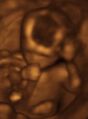

3D ultrasound of 3-inch (76 mm) fetus (about 14 weeks gestational age)

Obstetric ultrasonography is routinely used for dating the gestational age of a pregnancy from the size of the fetus, determine the number of fetuses and placentae, evaluate for an ectopic pregnancy and first trimester bleeding, the most accurate dating being in first trimester before the growth of the foetus has been significantly influenced by other factors.[22] Ultrasound is also used for detecting congenital anomalies (or other foetal anomalies) and determining the biophysical profiles (BPP), which are generally easier to detect in the second trimester when the foetal structures are larger and more developed.[23]

X-rays and computerized tomography (CT) are not used, especially in the first trimester, due to the ionizing radiation, which has teratogenic effects on the foetus.[24] No effects of magnetic resonance imaging (MRI) on the foetus have been demonstrated,[25] but this technique is too expensive for routine observation. Instead, obstetric ultrasonography is the imaging method of choice in the first trimester and throughout the pregnancy, because it emits no radiation, is portable, and allows for realtime imaging.[26]

The safety of frequent ultrasound scanning has not been confirmed. Despite this, increasing numbers of women are choosing to have additional scans for no medical purpose, such as gender scans, 3D and 4D scans.[27] A normal gestation would reveal a gestational sac, yolk sac, and fetal pole.[28]

The gestational age can be assessed by evaluating the mean gestational sac diameter (MGD) before week 6, and the crown-rump length after week 6. Multiple gestation is evaluated by the number of placentae and amniotic sacs present.[29]